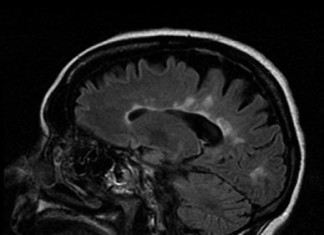

Estudio indica que el cerebro juega papel en la regulación de...

Los investigadores del Albert Einstein College of Medicine han demostrado por primera vez que el cerebro juega un papel clave en la regulación de la glucosa (azúcar) en el metabolismo de los seres humanos. Los resultados,...